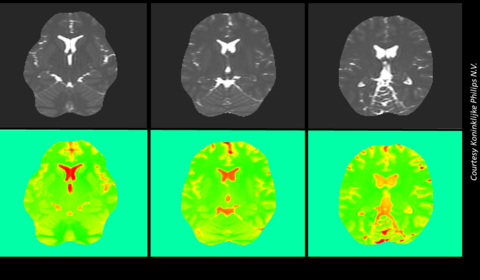

Quantifying the uncertainty of Electric Properties Tomography in medical imaging

Magnetic Resonance Imaging (MRI) is a diagnostic, mainly qualitative, technique used to visualise the soft tissues of a patient. The application of a strong magnetic field causes the protons in a patient’s hydrogen atoms to align with it. Radiofrequency pulses are then used to force the protons to move out of and back into alignment with the field,...